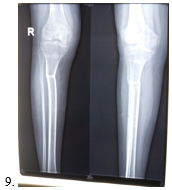

1, 2 & 3 Pre-operative x-ray of pelvis & both lower limbs. 4. CORA analysis.

5 & 6 Post-operative x-ray 7 & 8 Follow up x-ray.

9. Final x-ray.

A 15 years old adolescent girl came with the complaints of abnormal walking due to right knee bending inwards, also during standing position. She was perceived pain in right knee during walking and longtime standing position. She has H/O- fractured proximal tibia (Rt.) more than 6 months ago due to trauma and treated conservatively by long leg full plaster. Plaster removed after 3 months. One month later she developed pain in knee joint during walking and right knee gradually bend inwards. After more than 6 months of her primary fracture, when the problems worsening she was came to us with above complaints. O/E- Bil genu valgus right > left. Clinically, right knee -300 and left knee -100 valgus. There was 1.5 cm shortening of right lower limb than left. Previous fractured x-ray was not found. Both right and left lower limb with pelvis full radiograph was done. In x-ray both femurs and knee joints were normal. In radiograph, the medial and lateral surfaces of right tibia with fibula bend medially. Left tibial surfaces and fibula appears almost normal. The right tibia at the point of 14 cm from upper end there was maximum angulation point. The degree of genu valgus was evaluated by CORA method and treatment plan set accordingly. There was 300 medial bending of right tibial shaft and about 100 of left tibial shaft. The patient was diagnosed as post traumatic unilateral right tibial genu valgus following proximal tibia fracture.